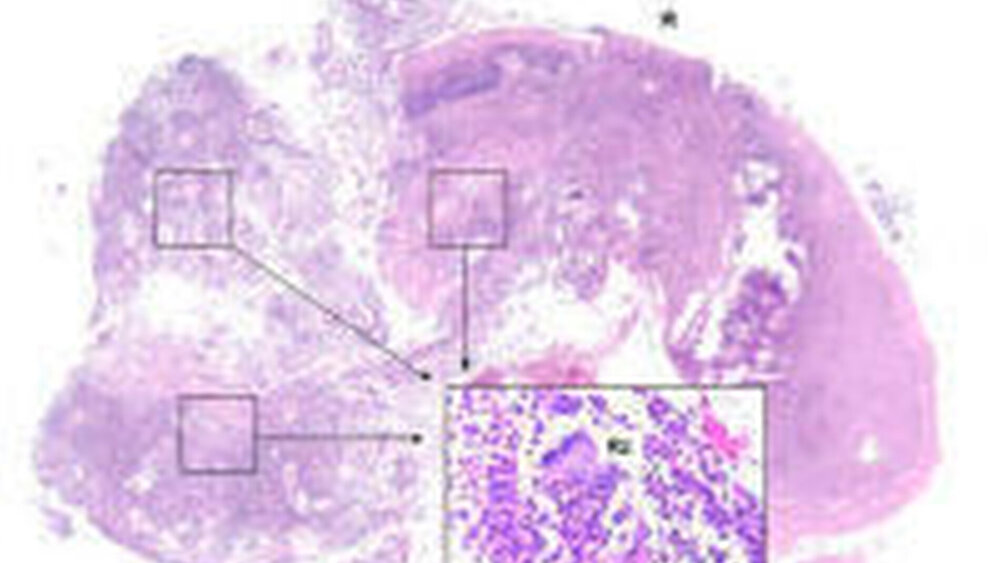

Die im Anschluss durchgeführte Probeexzision vom Ulkusgrund einschließlich Randsaum stellte sich bei der feingeweblichen Untersuchung als eine schwergradige, akut ulzeröse Stomatitis mit mehreren geordneten Riesenzellen ohne die vollständige Ausbildung von Epitheloidzellgranulomen dar (Abbildung 2).

Im Mund kann sich der Morbus Crohn als orofaziale Granulomatose (OFG), wie im oben beschriebenen Fall, mit enoralen Ulzerationen manifestieren. Schwellung der Lippen und der unteren Gesichtshälfte mit Lymphadenitis sowie hyperplastischer Gingivitis fehlten im vorliegenden Kasus, können aber als weitere Symptome auftreten [Wiesenfeld et al., 1985; Sciubba and Said-Al-Naief, 2003]. Ein Pflastersteinrelief der Mundschleimhaut, eine Lingua plicata und Geschmacksstörungen lagen bei der vorgestellten Patientin nicht vor, zählen aber ebenfalls zum Symptomenkomplex einer orofazialen Granulomatose und können auf einen Morbus Crohn hinweisen (Tabelle) [Rogers, 1996; Sciubba and Said-Al-Naief, 2003]. Histologisch werden orofaziale Granulomatosen durch ein Lymphödem der oberen Hautschichten, nicht verkäsende Granulome mit Riesenzellen oder eine perilymphatische lymphozelluläre Infiltration charakterisiert [Alawi, 2005], welche sich auch bei oben beschriebener Patientin nachweisen ließen.